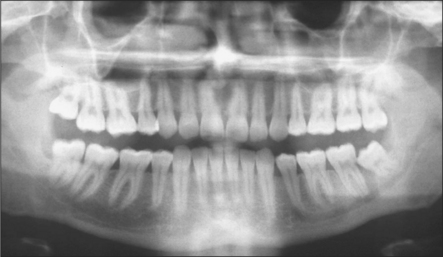

Lower third molars may be impacted mesioangularly (Fig. 5.3, right), vertically (Fig. 5.6), distoangularly (Fig. 5.3, left), horizontally (Fig. 5.10) or ectopically placed.

One simple method of determining the type of impaction involves comparing the distance between the roots of the third and second molar (a) with the distance between the roots of the second and first molars (b) (Fig. 5.11). If (a) is greater than (b) it is a mesioangular impaction; where (a) is less than (b) it is a distoangular impaction; where (a) is equal to (b) it is a vertical impaction. If the first molar is missing, the impaction can be determined by comparing a line drawn down the long axis of both the second and third molars: if parallel, it is vertical; if lower 8 leans towards lower 7 it is mesioangular; if the lower 8 long axis diverges from that of the 7, then it is a distoangular impaction.

image

Fig. 5.11 The author’s method to determine the type of impaction of a third molar by reference to spacing between the roots of the molar teeth. See text for details.